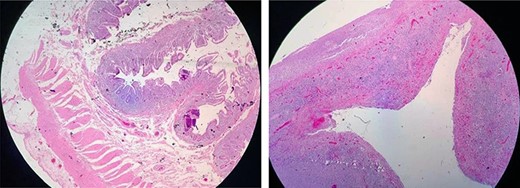

The surgical histopathology report was negative for malignancy and showed reactive changes with decreased villi crypts; a severe mixed inf lammatory infiltrate of the lamina propria was predominantly lymphoplasmacytic with accumulation o eosinophils and histiocytes,whichwere indicative of acute ulcerative ileitis with perforation. No microorganisms were identified (Fig. 2). Intestinal traffic was restored at 10 weeks. A side-to-side jejunocecal anastomosis was performed. The patient showed good evolution with a gluten-free diet and an improved clinical outcome. The patient was discharged from the surgical ward and scheduled for follow-up at the Department of Gastroenterology.